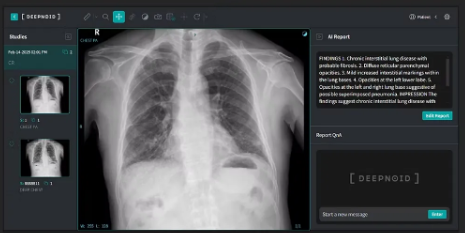

M4CXR(Multimodal for Chest X-ray)은 생성형 AI 기반의 흉부 X-ray 판독문 생성 솔루션으로, 결절·종괴, 경화, 섬유화, 무기폐, 폐기종, 결핵, 흉막 삼출, 기흉, 심비대, 림프절 비대, 늑골 골절, 기복증 등 80여가지 이상에 대한 소견을 제공한다.

주요 기능은 △종합적 판단 소견서 제공 △사용자 맞춤형 판독문 스타일 선택 △정면 및 측면 이미지 동시 처리 등이다.

폐와 심장, 종격동, 골격, 복강 등 흉부 X-ray에서 보이는 다양한 부위의 이상 소견을 빠짐없이 기술하며, 사용자 선호에 따라 자세한 스타일(Verbose style)과 간결한 스타일(Concise style) 중 선택하는 사용자 맞춤형 경험을 제공한다.

특히 PA(Posterior-Anterior)와 Lateral 영상을 동시 분석해 하나의 판독문을 제시함으로써 판독의 신뢰도를 높였다.